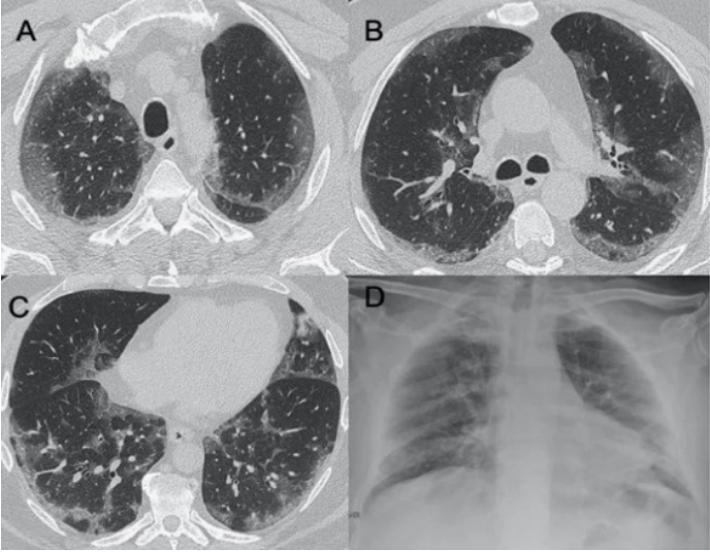

病毒性肺炎是由各种呼吸道病毒感染引发的肺实质炎症,容易并发呼吸衰竭,常见于幼儿(<5岁)和年龄>50岁的成人。WHO数据显示:社区获得性肺炎(CAP)中病毒性肺炎占20%~40%,在ICU中比例稍高,为30%~40%。常见病毒性肺炎的病原体包括流感病毒、鼻病毒、呼吸道合胞病毒、腺病毒、人偏肺病毒、巨细胞病毒、冠状病毒等。病毒性肺炎的常见影像学特征如下:图1所示为COVID-19的高分辨率CT(HRCT):在急性期,图1A为双肺弥漫性磨玻璃影(GGO),图1B为小叶周围型,图1C和D表现为亚急性间质性肺炎,GGO减少,主要为胸膜下局灶性实变和小叶间/小叶内间质增厚。图2A-C显示了一例与COVID-19间质改变相似的甲型流感病例:GGO主要分布在胸膜下和双侧,呈小叶周围性分布。图2D为同一患者的仰卧位胸片,可见弥漫性肺间质受累。图3A-D为一例H1N1相关肺炎并发急性呼吸窘迫综合征(ARDS)的影像,可见弥漫性、双侧GGO以及牵拉性支气管扩张。图4A显示了一例急性腺病毒肺炎,具有典型的多灶性和大叶GGO,图4B-C显示其导致的长期后遗症——Swyer–James综合征的表现。图5所示为一例疱疹病毒性肺炎,可见双侧分布呈斑片状的GGO(主要位于两肺上叶)。一项基于对美国大规模人群分析的前瞻性多中心研究显示,病毒性肺炎的患病率和发病率随年龄而异,其累积发生率约为22%。研究纳入2222例儿童,其中66%(共1472例)报告有病毒感染,在155例(7%)病例中发现病毒和细菌合并感染。事实上,呼吸道病毒、腺病毒和人偏肺病毒在5岁以下儿童中比较常见。在同一研究的2259例成年人患者中,只有853例(38%)患者检测到病原体,530例(23%)患有病毒性肺炎,59例(3%)发现合并感染。